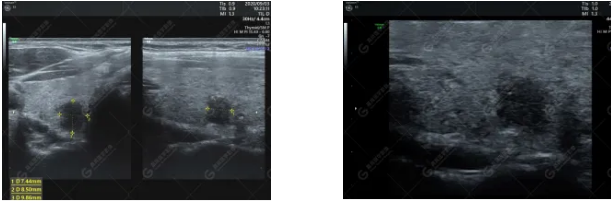

超聲圖像

二維超聲:右側(cè)葉探及低回聲結(jié)節(jié),邊界欠清,形態(tài)欠規(guī)則,縱橫比>1,內(nèi)可少許細(xì)點(diǎn)狀強(qiáng)回聲,后方回聲無(wú)明顯變化。

CDFI:結(jié)節(jié)周邊可見(jiàn)少許細(xì)條狀血流信號(hào),內(nèi)部未見(jiàn)明顯血流信號(hào)。